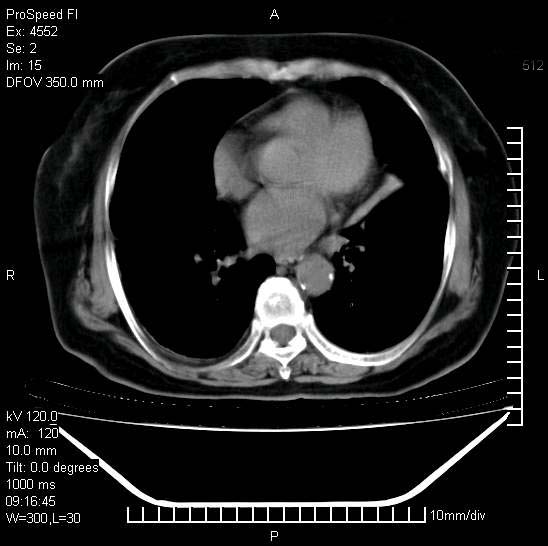

十几年前曾患肺结核,一周前突咳血约100ml,中性粒细胞稍高,诊断两上肺陈旧结核,下肺炎症,给予抗炎治疗,近几日晚上高热,39度,仍咳少量血,4天前ct及今天ct上传。

[face=黑体]8月30日[/face]

1)两肺结核并感染。2)不排除左肺上叶中央型肺癌并阻塞性肺炎、肺不张可能;建议行纤支镜检查。3)右肺门及纵隔淋巴结肿大。4)双侧胸腔积液。